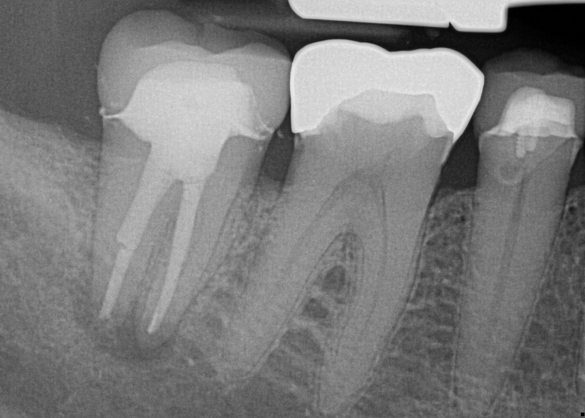

A patient had been seen for caries control and replacement of deteriorating amalgam restorations. Two weeks postoperatively, the patient was unable to tolerate hot or cold temperatures and was unable to chew any type of food (Figure 5). The patient accepted endodontic therapy, post and core, and full-crown coverage at a later date. The principles of the rotary-file system were used again.

Fig 5. Preoperative No. 14 maxillary left first molar.

Figure 5